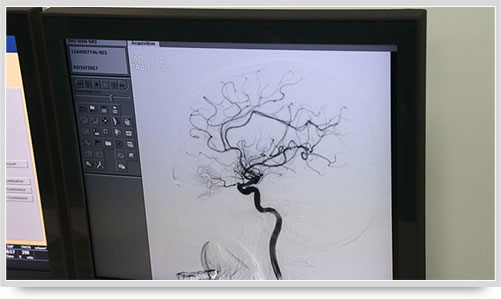

同时,手术台前的液晶显示仪屏幕上清晰地现显出导管的路径,在李主任的操作下准确到达指定检查部位,各条血管的“庐山真面目”清晰可见。

弓上造影、超选到颈内动脉、椎动脉......在数字减影技术下,注入显影剂后,导管经患者右侧股动脉在体内推进,由于股动脉离脑血管距离较远,中间“路程复杂”,对施术医生的要求非常之高。

全脑血管造影术(DSA)是运用数字减影技术下进行的全脑血管摄片,因此又称数字减影血管造影。技术上一般采用局部麻醉,右侧股动脉穿刺、置管,再将一根造影管通过腹主动脉、主动脉弓,选择性进入左右颈内动脉和椎动脉后,分别造影,发现病灶后还应行三维血管造影。造影图像较以往所用的常规脑血管造影所显示的图像,更清晰和直观,一些精细的血管结构亦能显示出来,是目前国际上公认的血管性疾病诊断的“金标准”。